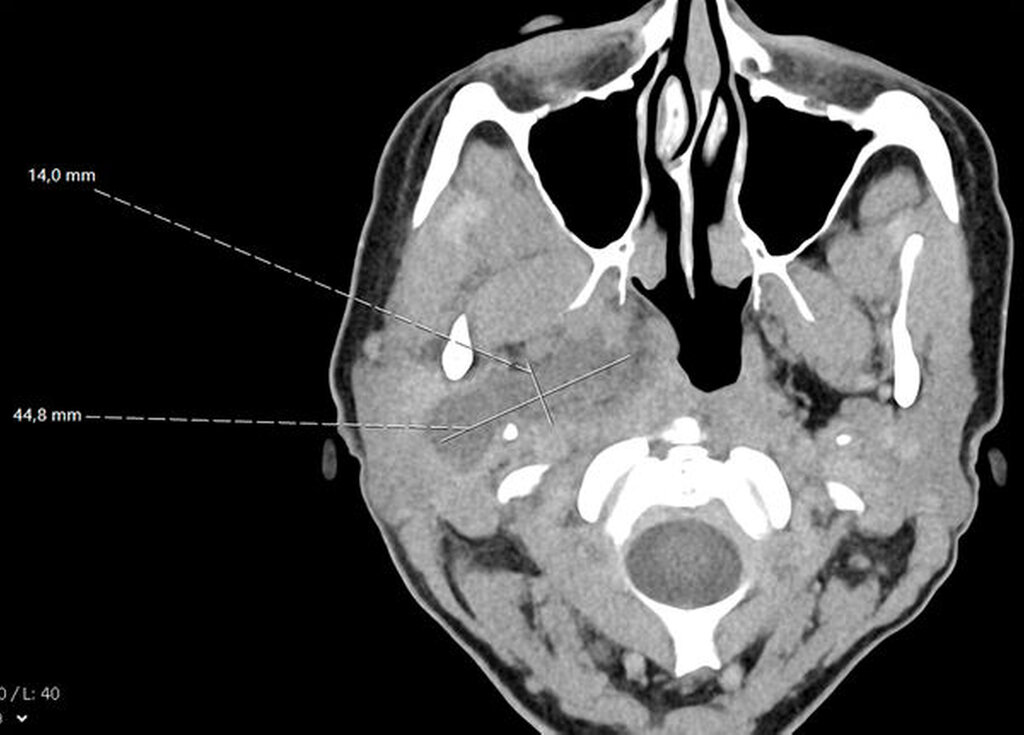

Sonografisch ließ sich weder von submandibulär noch von temporal eine klar abgrenzbare Abszessformation darstellen. Ein initial angefertigtes Labor zeigte stark erhöhte Entzündungsparameter mit einem C-reaktiven Protein von 261 mg/l (Normwert < 5 mg/l) sowie einer Leukozytose von 18/nl (Normwert 3,5–10/nl). Zur weiteren Diagnostik erfolgte die Anfertigung einer Computertomografie des Schädels mit Kontrastmittel. Hier zeigte sich eine circa 14 mm x 45 mm große, liquide Veränderung rechts im Musculus Pterygoideus mediales bis in die Glandula Parotis rechts reichend (Abbildungen 1 und 2). Aufgrund einer flauen Parenchymkontrastierung ließ sich eine Abszessformation nicht sicher ausschließen, die Befunde sprachen in Zusammenschau mit dem zeitlichen Ablauf und der stattgefundenen zahnärztlichen Behandlung jedoch in erster Linie für ein postinterventionelles Hämatom. Eine antikoagulatorische und/oder thrombozytenaggregatorische Therapie konnte ausgeschlossen werden.

Unmittelbar nach der stationären Aufnahme wurde mit der intravenösen Antibiotikatherapie, Glukokortikoidgabe und antiphlogistischen Maßnahmen begonnen. Daraufhin zeigten sich die klinischen und die laborchemischen Entzündungsparameter rückläufig. Die Mundöffnung der Patientin war bereits am Folgetag mit einer Schneidekantendistanz von 40 mm deutlich verbessert. Zur Verlaufskontrolle und Beurteilbarkeit des Weichgewebes im Bereich der Mastikatorloge wurde am zweiten Tag nach stationärer Aufnahme eine Magnetresonanztomografie des Kopfes durchgeführt. Im Vergleich zur initialen Computertomografie der Halsweichteile zeigte sich eine zunehmende Resorption der liquiden ovalären Veränderungen in der rechten Mastikatorloge (Abbildungen 3 und 4). Zum Ausschluss einer otorhinolaryngologischen Pathologie wurde die Patientin konsiliarisch in der Hals-Nasen-Ohrenheilkunde der Universitätsmedizin Mainz vorgestellt. Die Kollegen fanden keine pathologischen Auffälligkeiten, so dass bei radiologisch rückläufigem Befund von einem Hämatom ausgegangen werden konnte. Am vierten Tag nach stationärer Aufnahme konnte die Patientin die Klinik mit nahezu normwertigen Laborparametern verlassen und in die ambulante Nachsorge entlassen werden.